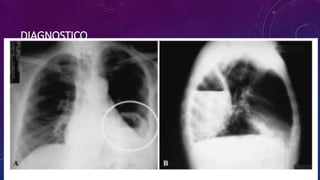

DIAGNOSTICO